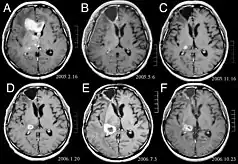

MRI of a patient with anaplastic astrocytoma.

The St Anne-Mayo grading system[4][6][7] also is used to grade astrocytomas; however, this system uses four morphologic criteria to assign a grade:

a) nuclear atypia,

b) mitosis,

c) endothelial proliferation-'piled-up' endothelial cells. NOT hypervascularity

d) necrosis.

The St. Anne-Mayo grade has four categories of tumors:

• Grade 1 tumors do not meet any of the criteria.

• Grade 2 tumors meet one criterion, usually nuclear atypia.

• Grade 3 tumors meet two criteria, usually nuclear atypia and mitosis.

• Grade 4 tumors meet three or four of the criteria.